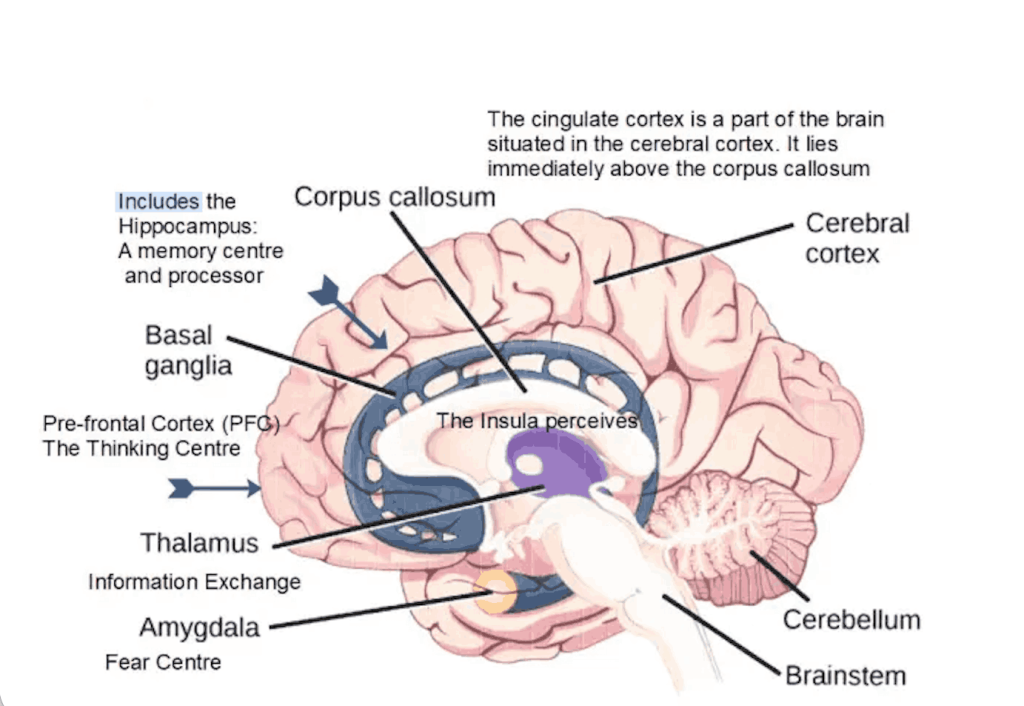

Коли ми отримуємо різке зауваження або стикаємося з осудом, першою реагує Амігдала — структура лімбічної системи, відповідальна за розпізнавання загроз.

Нижче зображення частин мозку, щоб більше уявити як все виглядає:

Також в мозку є Гіпокамп, він відповідає за:

Тому так і виходить, що при гострому стресі тимчасово знижується активність Префронтальної кори — області, відповідальної за:

У 2014 році в журналі Brain and Behavior було опубліковане дослідження, яке показало: у людей з високим SPS при перегляді емоційних стимулів активніше працюють:

- інсула

- ділянки, пов’язані з емпатією

- області, що відповідають за глибоку когнітивну обробку

Інсула — це центр інтероцепції, тобто здатності відчувати внутрішній стан тіла: серцебиття, напруження в грудях, стиск у горлі, нудоту, «клубок у животі», тепло/холод, внутрішнє тремтіння.

Тому вона вважається ключовою структурою для емоційної усвідомленості, емпатії, соціальної чутливості. І у високочутливих вона часто працює інтенсивніше.